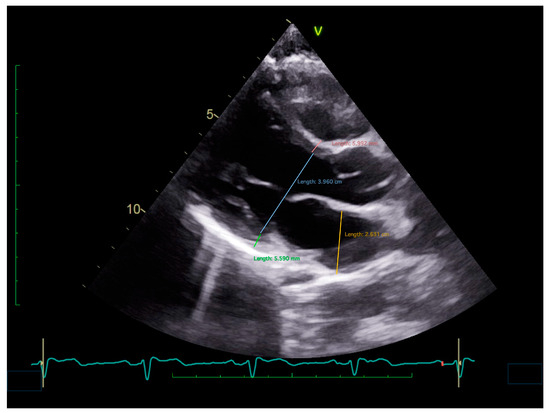

Figure 4.

An ultrasound image of a parasternal long-axis view of the heart, showing small left cavities and thin ventricular walls in a patient with reflex syncope.